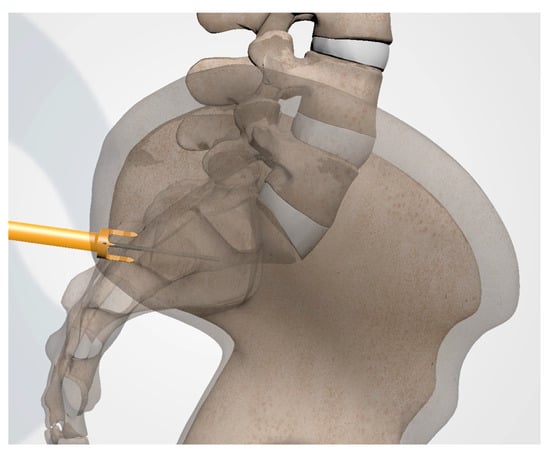

3.3.4. Steinman Pin Placement